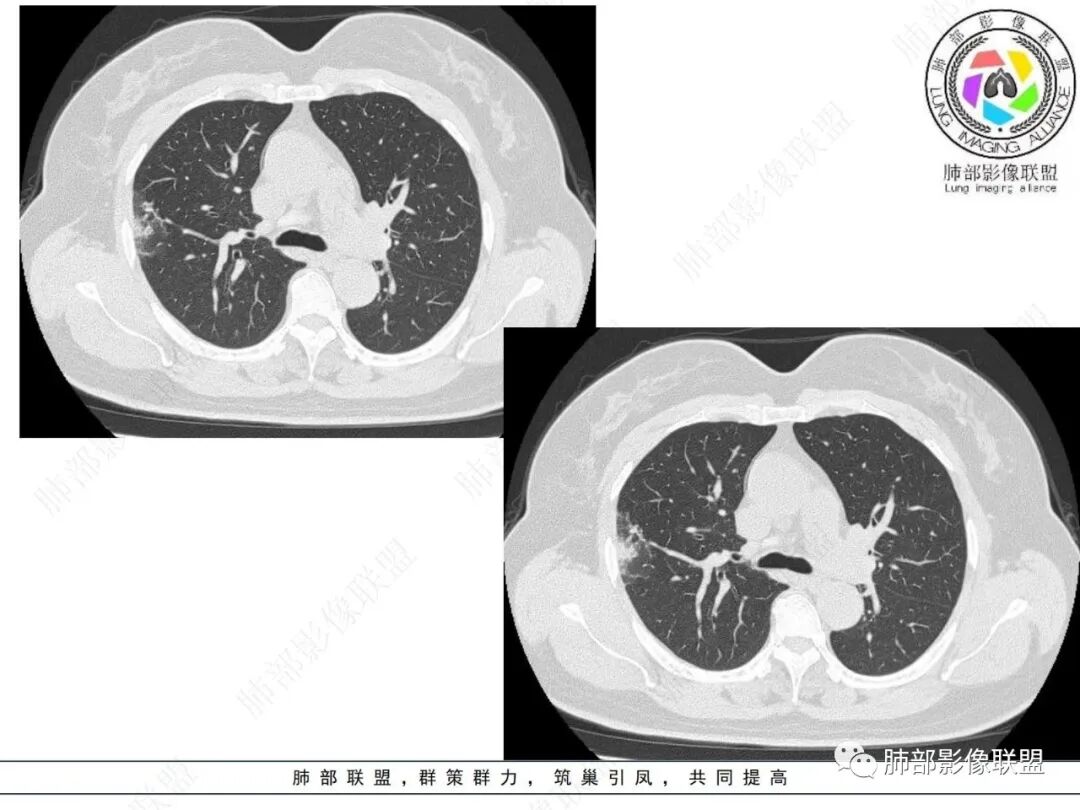

周围磨玻璃部分间杂条索状高密度区,密度欠均匀(可疑重力分布趋势),其磨玻璃影边界大多较清楚或可分辨,部分“L型”边缘,提示小叶间隔阻挡可能。血管穿行自如,可疑远端支气管进入。

实性部分较密实,不规则,隐约见棘突或刺状突起,未见钙化、空洞或液化区,实性边缘可见斑状略低密度间隙(借用王兆宇老师课件,称其呈“松软”的形态)。动脉期实性部分较明显不均匀强化,如果有完整增强图,还可以观察内部血管情况。

纵隔窗相对肺窗病灶相对小,仅部分实性影呈现。病灶张力不高,相邻胸膜增厚(糊墙),未见明显胸膜牵拉凹陷。

右肺上叶胸膜下混合磨玻璃结节,磨玻璃部分与实性部分密度都不均匀,病灶有重力分布效应,小叶间隔阻挡,收缩力羸弱。中老年女性,如此大范围病灶,缺乏临床表现,会让人警惕非感染性病变,尤其是恶性病灶可能!

病灶磨玻璃部分边界较清楚,有重力分布趋势,可能会想到黏液腺癌,或者分泌粘液的腺癌的可能性。不支持地方也有,如实性部分密度偏高,病灶强化程度偏高等。

其他需要鉴别的原有病灶伴出血,炎性病灶等等,感染性病变需要排除的尚有隐球菌,临床表现逍遥,病灶未出胸膜下,周围磨玻璃等等……